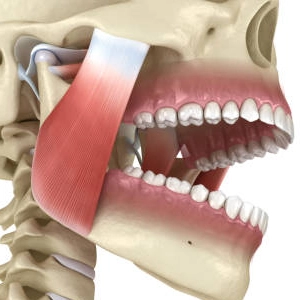

The Temporomandibular Joint (TMJ) is the hinge joint connecting your lower jawbone (mandible) to the skull, located just in front of each ear on both sides of your face. It enables chewing, speaking, and all jaw movements.

Temporomandibular Joint — The Jaw-Skull Hinge

The TMJ is one of the most complex joints in the human body, enabling chewing, speaking, and all jaw movements. Dysfunction here affects the entire oro-facial system.

• The jaw joint itself (articular disc, condyle)

• Masticatory muscles (chewing muscles)

• Surrounding nerves and ligaments

• Bite alignment (occlusion)

• Neck, shoulder and upper back muscles

• Sleep quality and airway function